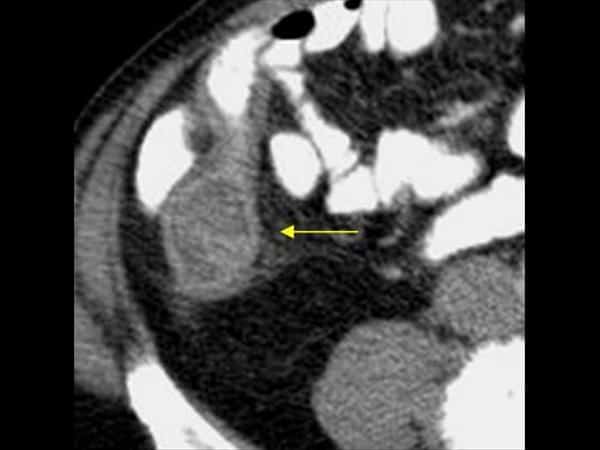

Mucocele ruột thừa

» Thông tin: Nam giới – 71 tuổi.

» Lâm sàng: Đau hố chậu phải mạn tính.